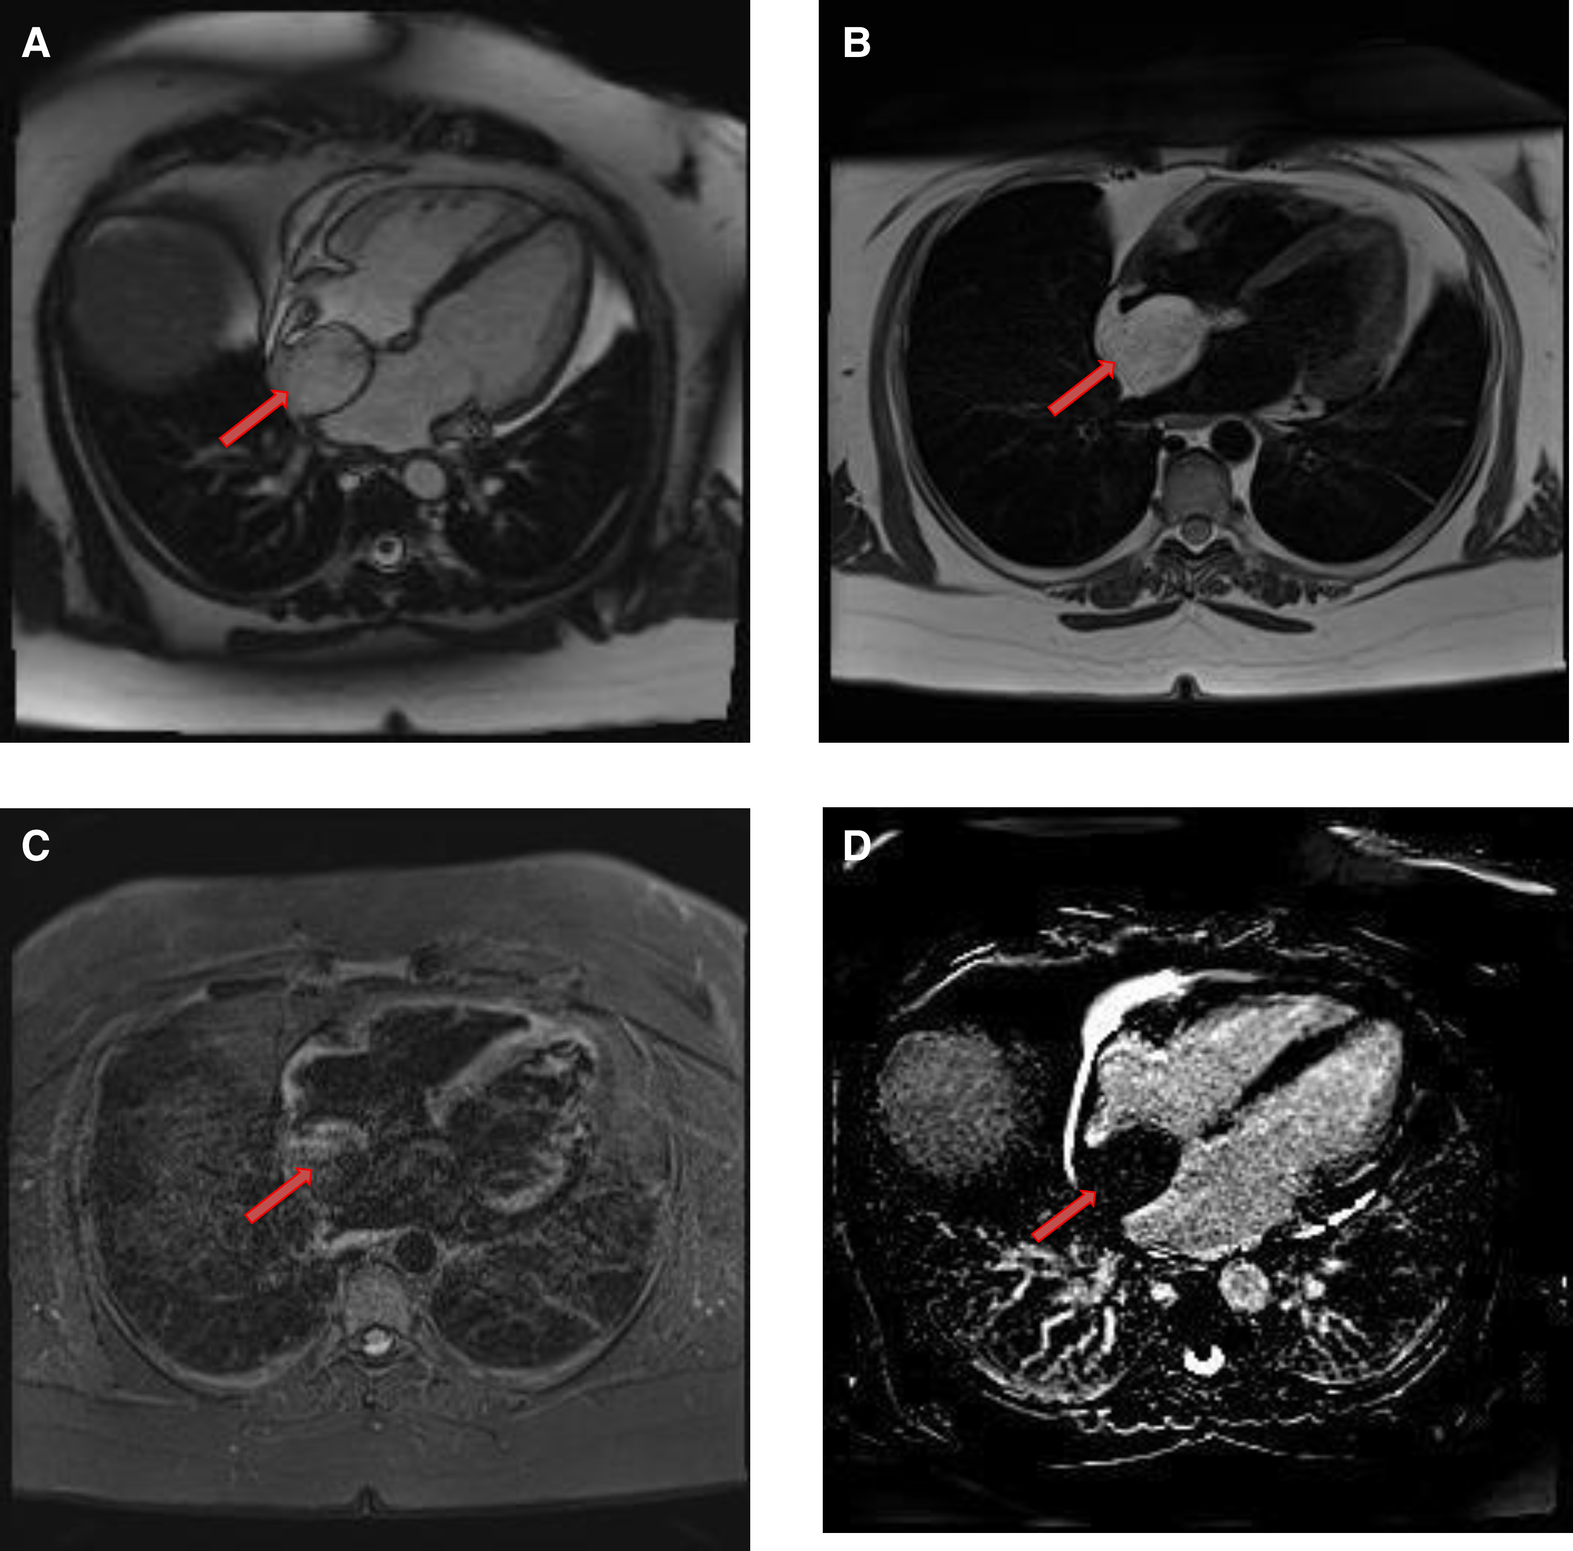

Figure 5

A 53-year-old male with lipomatous hypertrophy of the intra-atrial septum. (A) Cine CMR images showing diffuse enlargement and fatty replacement of the intra-atrial septum, consistent with lipomatous hypertrophy of the intra-atrial septum (red arrow). (B) Characteristic “dumbbell shaped” appearance of the mass on axial dark blood, double inversion recovery fast spin echo images (red arrow).

Figure 6

A 61-year-old male with lipomatous hypertrophy of the intra-atrial septum. (A) Cine CMR images showing diffuse enlargement and fatty replacement of the intra-atrial septum, consistent with lipomatous hypertrophy of the intra-atrial septum (red arrow). (B) Characteristic “dumbbell shaped” appearance of the mass on axial dark blood, double inversion recovery fast spin echo images (red arrow).

CMR provides a definitive diagnosis of both lipoma and lipomatous hypertrophy. Lipomas typically have a homogeneous appearance on CMR. Characteristically, they have the same signal intensity as surrounding chest wall fat on both T1- and T2-weighted images. Additionally, two extremely useful sequences are pre and post contrast fat saturated T1 Weighted sequences. Characteristically, signal dropout is observed on these sequences confirming the diagnosis of a fat-containing lesion. Due to their avascular nature, they do not show contrast enhancement on LGE images (Table 1 and Figures 7, 8).

Figure 7

A 68-year-old female with intra-atrial septal lipoma. (A) (On line video 3), CMR cine images showing a sharply marginated mass arising from the intraatrial septum (red arrow). (B) This mass has same signal intensity (high) as surrounding fat on axial T1-weighted, dark blood, double inversion recovery fast spin echo images (red arrow). (C) Fat suppression sequence representing suppression of surrounding fat (white arrow) as well as the mass in the intra-atrial septum (red arrow).

Figure 8

A 50-year-old female with intra-atrial septal lipoma. (A) This mass has signal intensity (high) as surrounding fat on axial T2-weighted, dark blood, double inversion recovery fast spin echo images (red arrow). (B) This mass is suppressed on axial triple inversion recovery images (red arrow). (C) Complete absence of contrast agent uptake on late gadolinium enhanced images (red arrow).